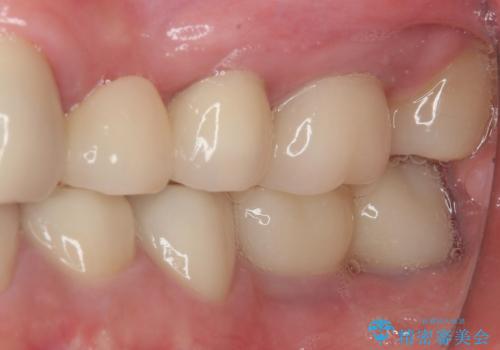

やはりむし歯は大きく、一部歯髄を切除することとなりましたが、その後は良好な経過をたどっています。